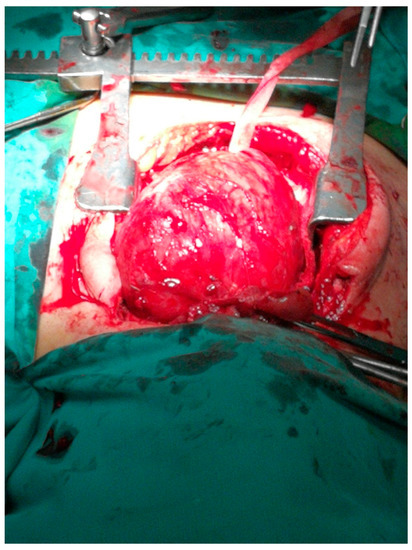

Cardiopulmonary Arrest Caused by Large Substernal Goiter—Treatment with Combined Cervical Approach and Median Mini-Sternotomy: Report of a Case

Koulouris, C.; Paraschou, A.; Manaki, V.; Mantalovas, S.; Spiridou, K.; Spiridou, A.; Laskou, S.; Michalopoulos, N.; Radu, P.A.; Cartu, D.; et al. Cardiopulmonary Arrest Caused by Large Substernal Goiter—Treatment with Combined Cervical Approach and Median Mini-Sternotomy: Report of a Case. Medicina 2021, 57, 303. https://doi.org/10.3390/medicina57040303